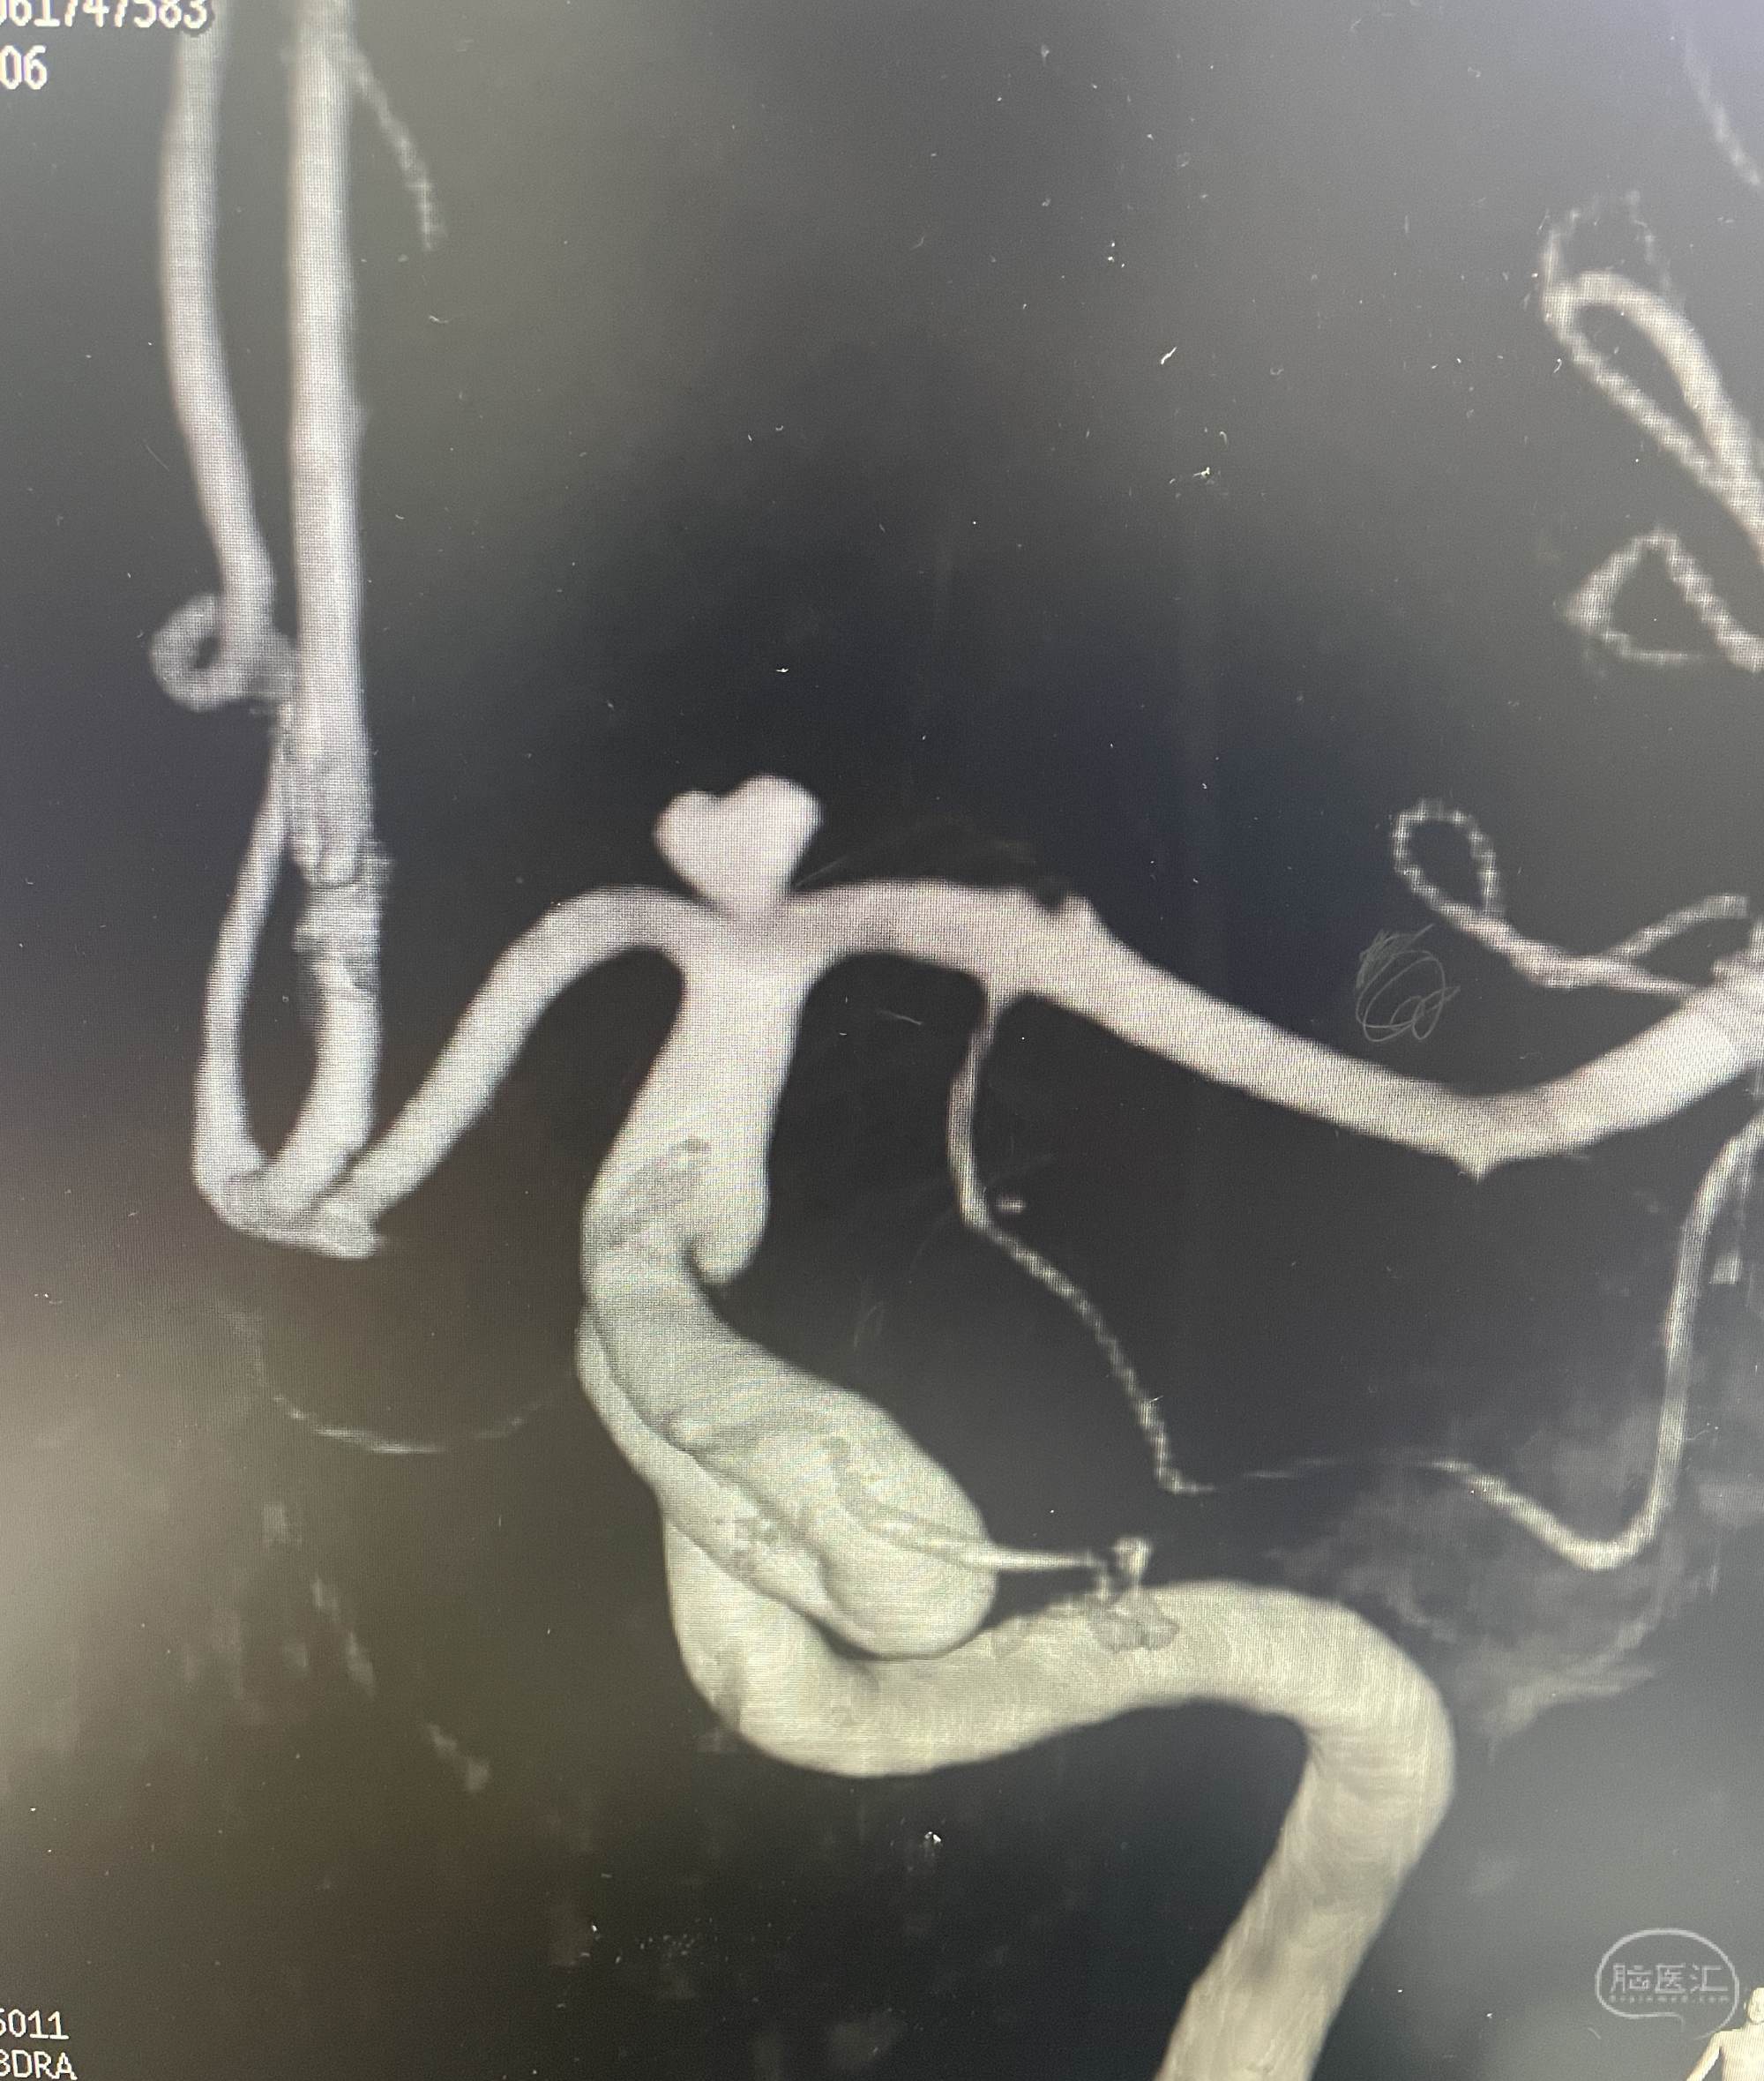

DSA提示右侧后交通动脉瘤,左侧颈内动脉末端动脉瘤,左侧后交通圆锥,左侧海绵窦夹层动脉瘤。

下面这个动脉瘤像不像一颗爱心,可是它很“凶残”。随时可能破裂出血,危急患者生命。

我们术中先解决右侧后交通责任动脉瘤,再解决左侧颈内动脉末端以及海绵窦夹层动脉瘤,手术顺利,动脉瘤消失,可谓一箭三雕🐮!